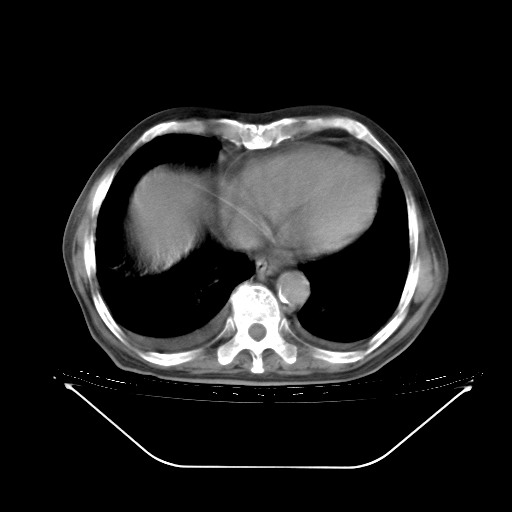

今天复查肺部CT,发现双肺广泛磨玻璃样改变。所以我把3月19日和5月9日相隔50天的肺部CT上传。请大家会诊。

5月9日肺部CT(在4月27日齐鲁医院肺部CT描述部分肺组织磨玻璃样改变,12天后肺组织广泛磨玻璃样改变)

大致读了系列胸部CT:纵隔窗无明显异常,肺窗:从4、27至今:主要是双肺中下野外带可见毛玻璃样改变,目前处于急性肺泡炎阶段,至于原因考虑1、结替组织或胶原血管性疾病所致?2、恶性疾病如恶组在肺部所致的表现或细支气管肺泡癌?3、药物或其它原因如肺蛋白沉着症所致肺泡炎目前不太可能?总之,明天就去请我院的呼吸科、感染科、血液科和临免专家会诊哈。